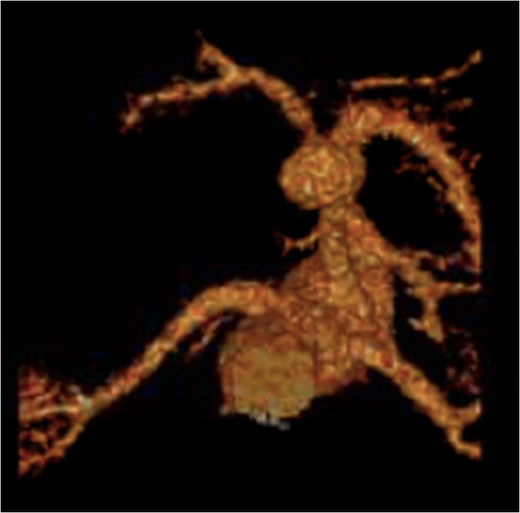

Recreated 3D imaging of the aneurysm arising from the ventral aspect of the distal celiac artery.